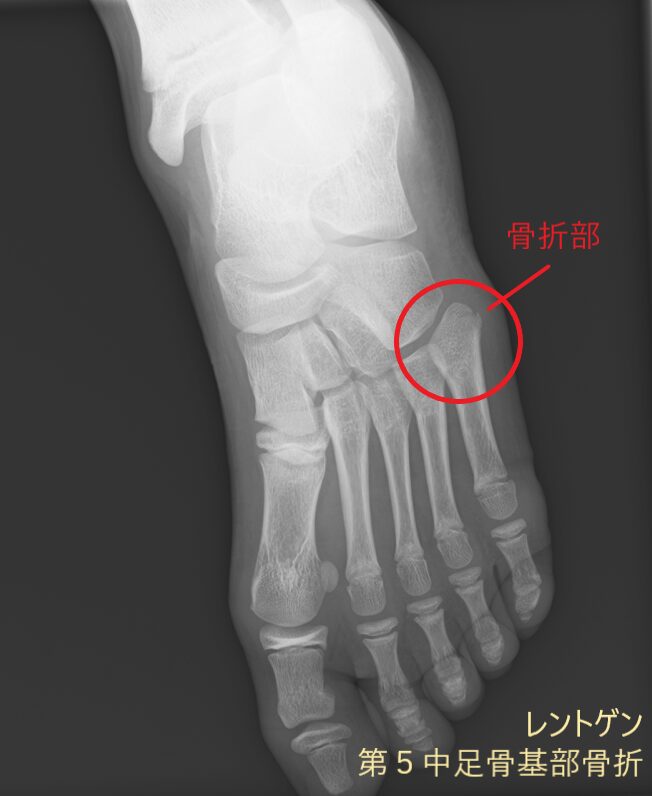

レントゲン画像には映りにくい筋肉や腱、靭帯などの状態に加え、骨の様子もあわせて確認できます。